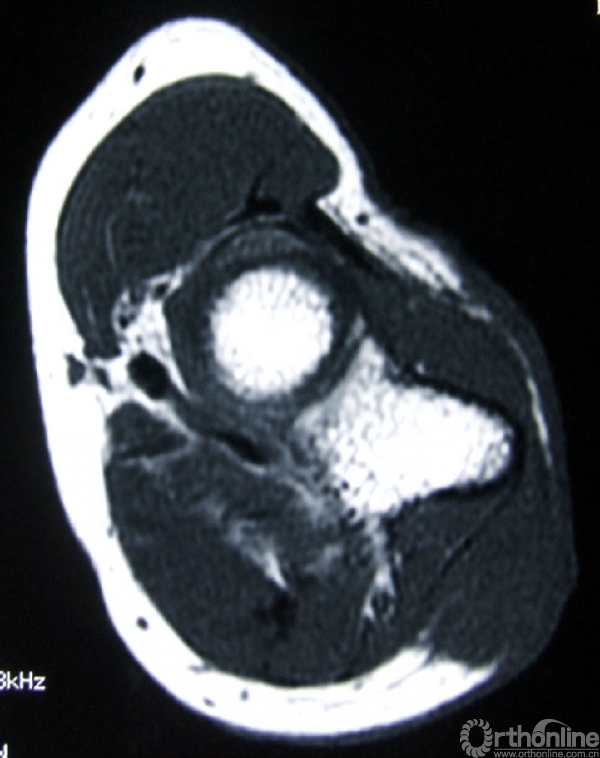

3.辅助检查:化验检查未见明显异常。B超显示右肘关节后方软组织内可见实性杂乱回声包块,1.5cm×1.0cm,界欠清,其内回声不均,可见少许血流信号。手术切口上端深处紧贴尺骨可见低回声小包块,0.9cm×0.2cm,未见血流信号。MRI(图2)示右肘关节后方皮下组织内可见软组织肿块影,边界不甚清楚,T1加权像呈现低信号,T2加权像呈中高信号,增强后T1加权像呈高信号,抑脂像亦呈现高信号。会诊病理(图3)显示成片较密集的轻度-中度间变的短梭形细胞,纤维性间质局部粘液变。初步考虑梭形细胞肉瘤Ⅱ级,可符合恶性外周神经鞘瘤形态。

图2a:T1加权像

图2b:增强后T1加权像

图2c:T2加权像

图2d:抑脂像